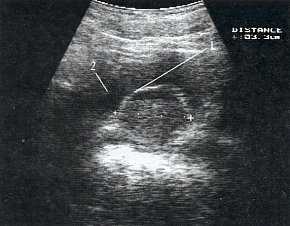

В марте 2002 г. в связи с эпизодом лейкоцитурии лечился у нефролога; при контрольном УЗИ впервые диагностированы изменения в мочевом пузыре и паравезикально слева. При повторном УЗИ выявлено (рис. 1а): правая почка увеличена в размерах (длина 12,7см; толщина паренхимы 1,6 см); чашечно-лоханочная система не расширена. Левая почка отсутствует. Стенки мочевого пузыря не изменены; в просвете слева определяется округлое образование 3,5 x 4,6 x 5,0 см с неоднородным содержимым (объем около 40 мл). Заключение: аплазия левой почки; уретероцеле слева.

а) Эхограмма.

Компьютерная томография (КТ): в проекции устья левого мочеточника и на фоне мочевого пузыря слева определяется дополнительная тень 3,1 x 4,0 x 4,0 см с четкими контурами и плотной стенкой. Мочеточник выше устья расширен до 1 см. Заключение: КТ-картина уретероцеле слева, уретерэктазия слева (рис. 1 б, в).